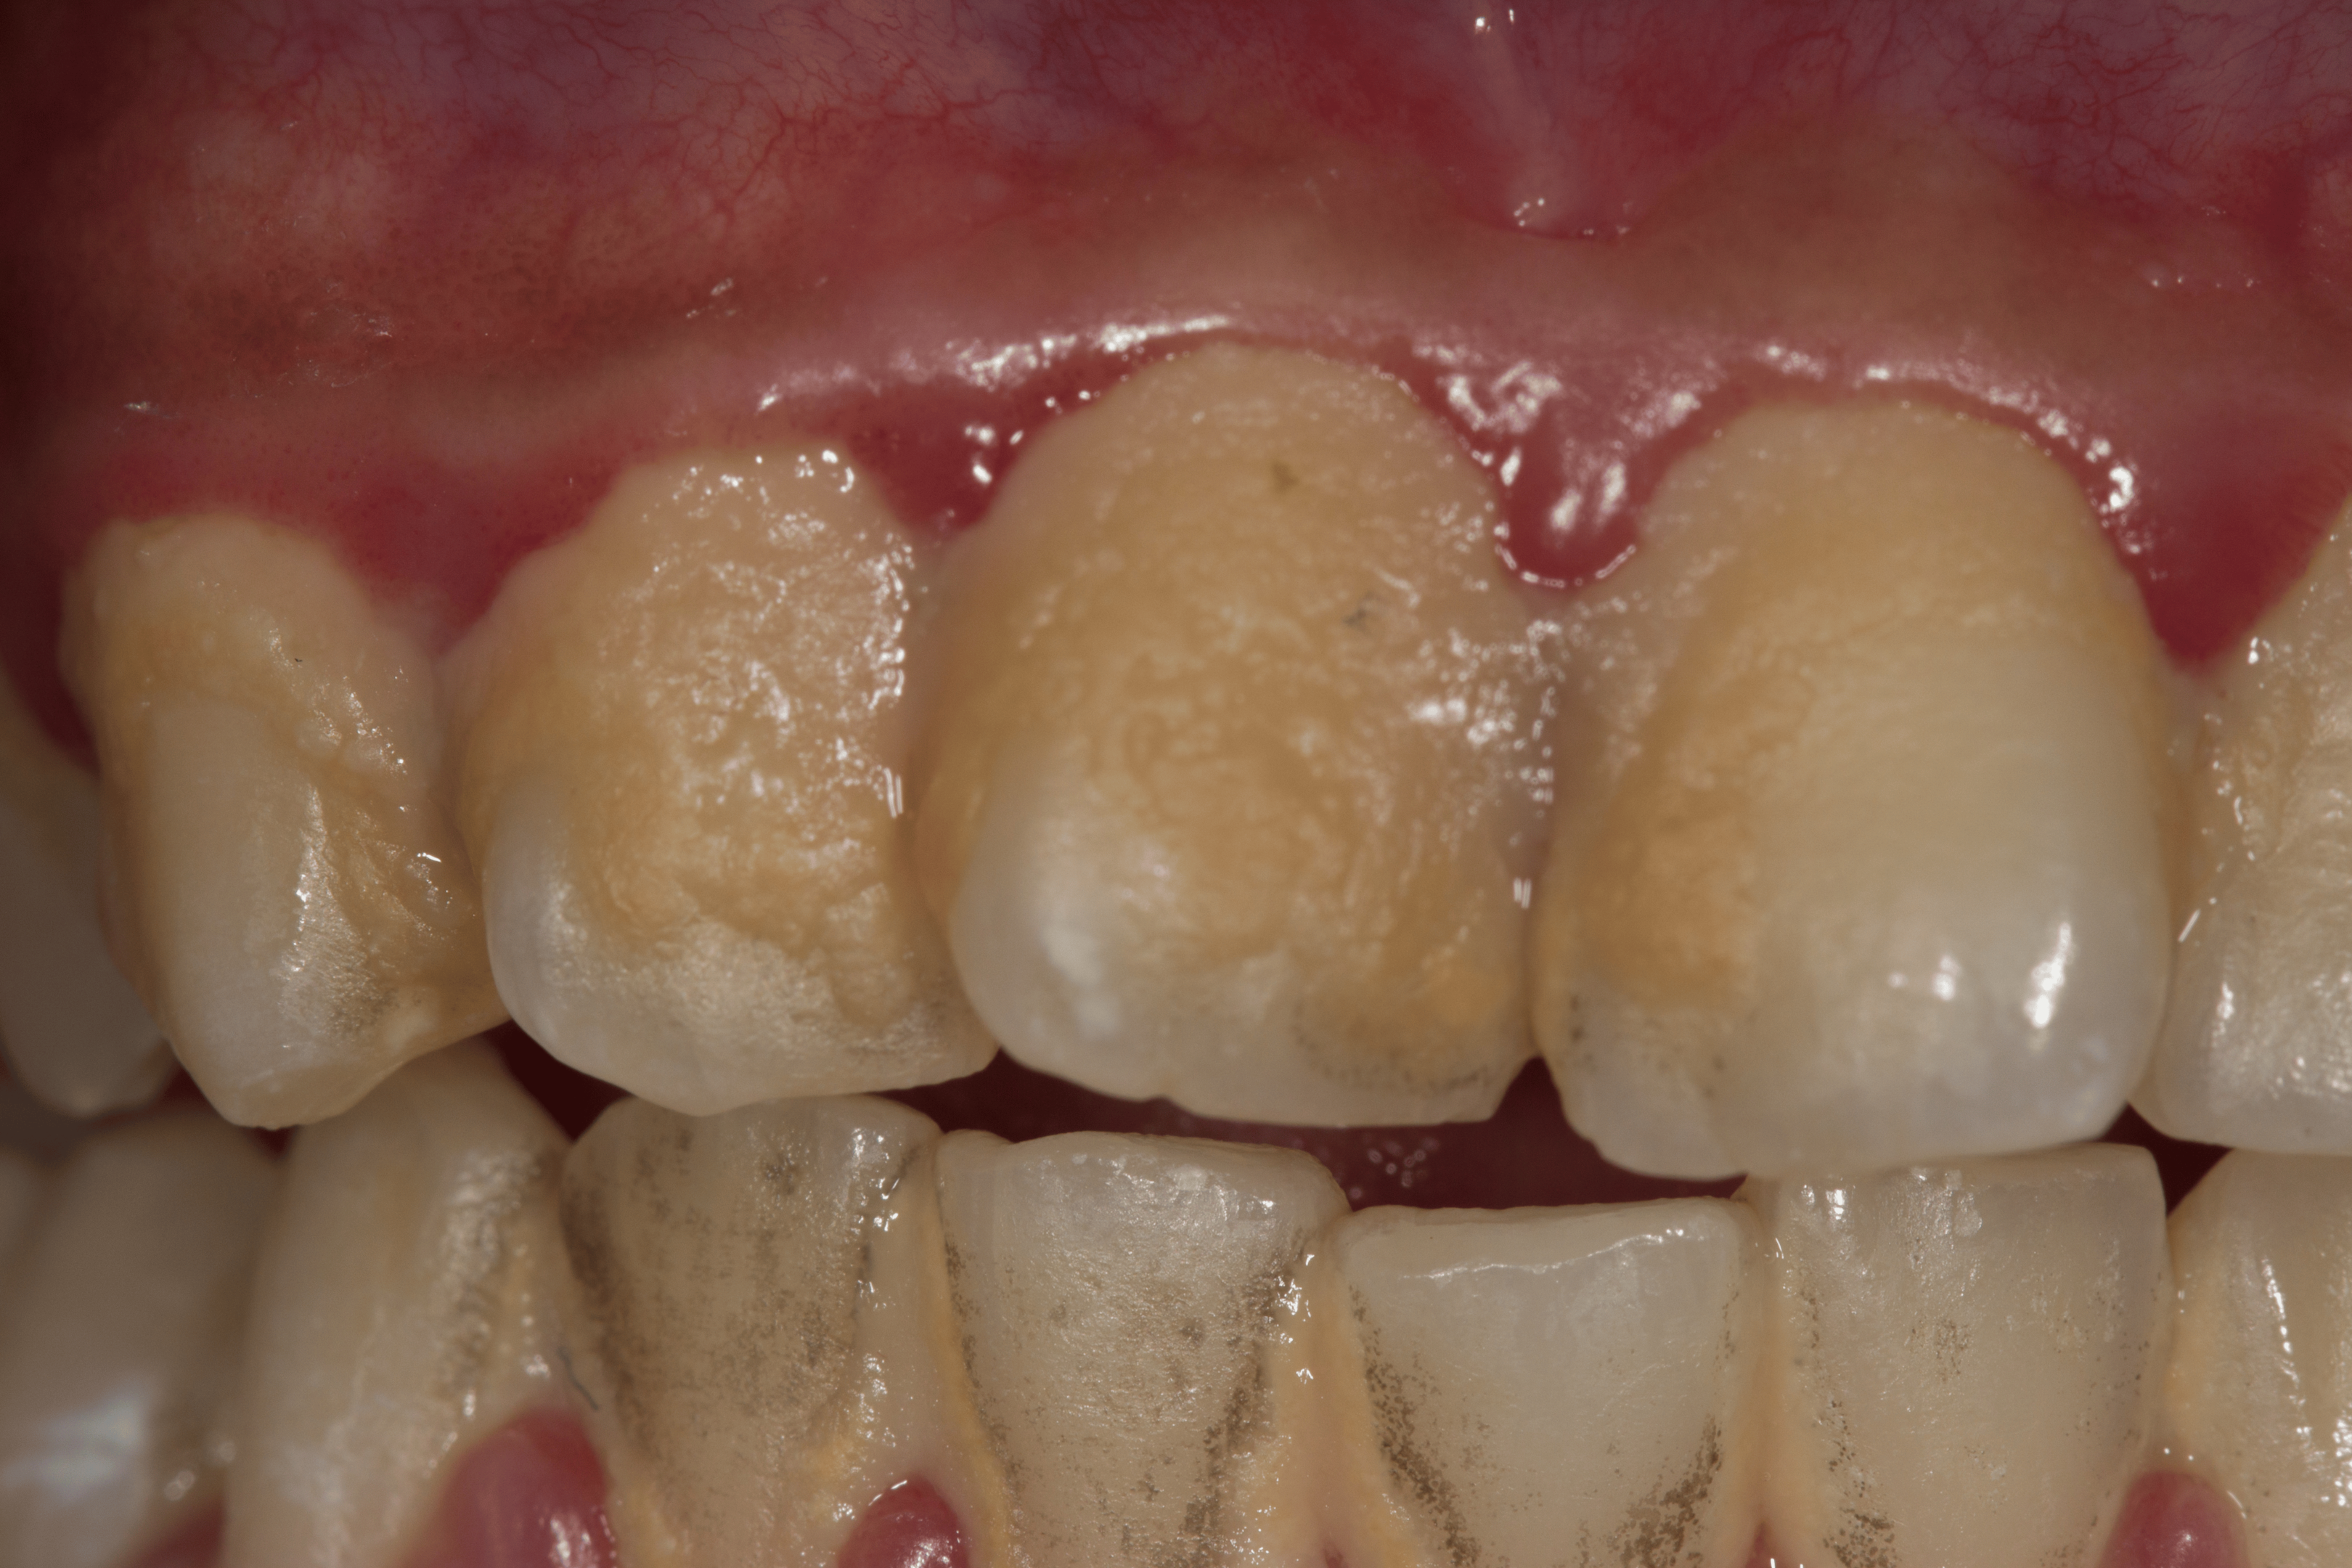

Det finnes to typer: supragingival (over tannkjøttlinjen) og subgingival (under tannkjøttlinjen). Supragingival er synlig på baksiden av fortennene og langs tannkjøttlinjen, mens subgingival ligger skjult under tannkjøttet og er vanskeligere å oppdage uten en profesjonell undersøkelse.

Det kan være vanskelig å merke på egen hånd, men du kan se etter gule eller brune flekker langs tannkjøttlinjen eller mellom tennene.